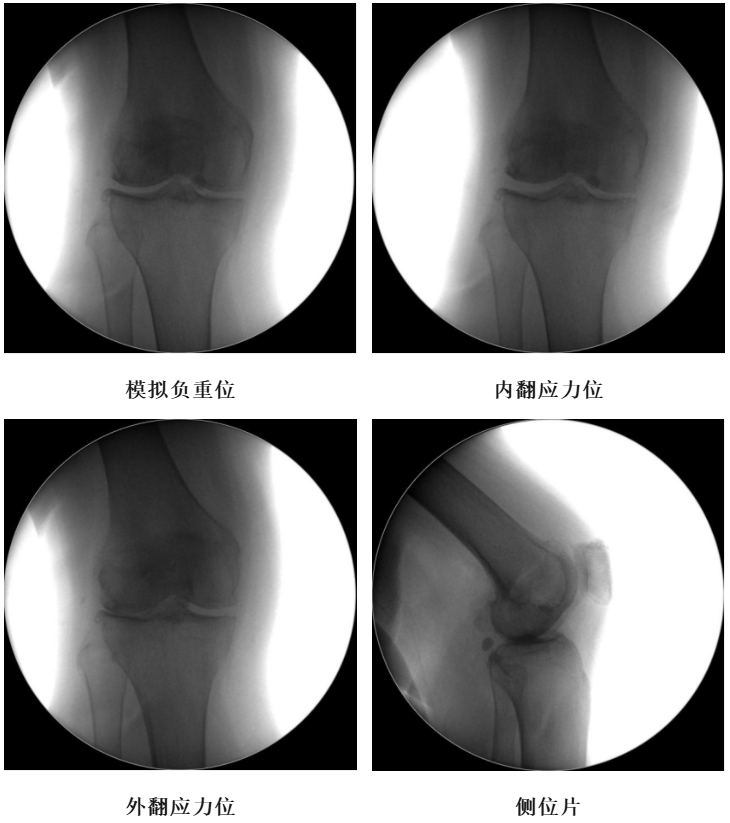

术前透视片

体格检查:右膝外翻畸形,约6°,无屈曲畸形。屈曲20°内翻应力下外翻畸形可纠正,屈曲90°可自行纠正。外侧关节间隙处压痛阳性。活动度:0°~115°。

X-Ray:右膝外侧间隙明显狭窄,站立位外侧间隙消失,内侧间隙正常,膝关节稳定。